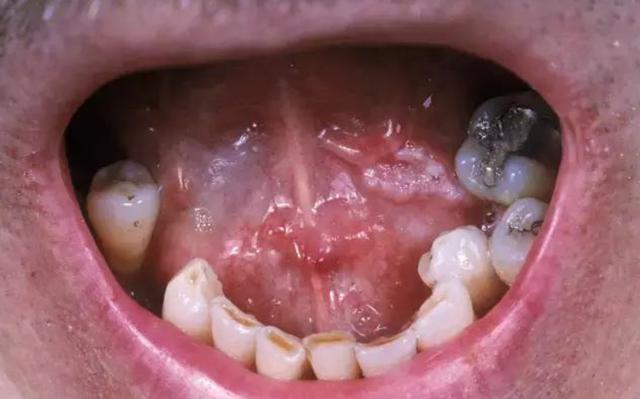

如果你长期吃槟榔,已经出现舌头不灵活,说话口齿不清或嘴张不开的情况,那你就要小心了。

口腔癌 前兆: 口腔溃疡是癌的“保护伞”

在临床上,很多癌患者是因为自觉“口腔溃疡”难愈,疼痛难忍,才决定去医院检查,最终被确诊为口腔癌。通常来讲,口腔溃疡就是口腔癌的前兆。